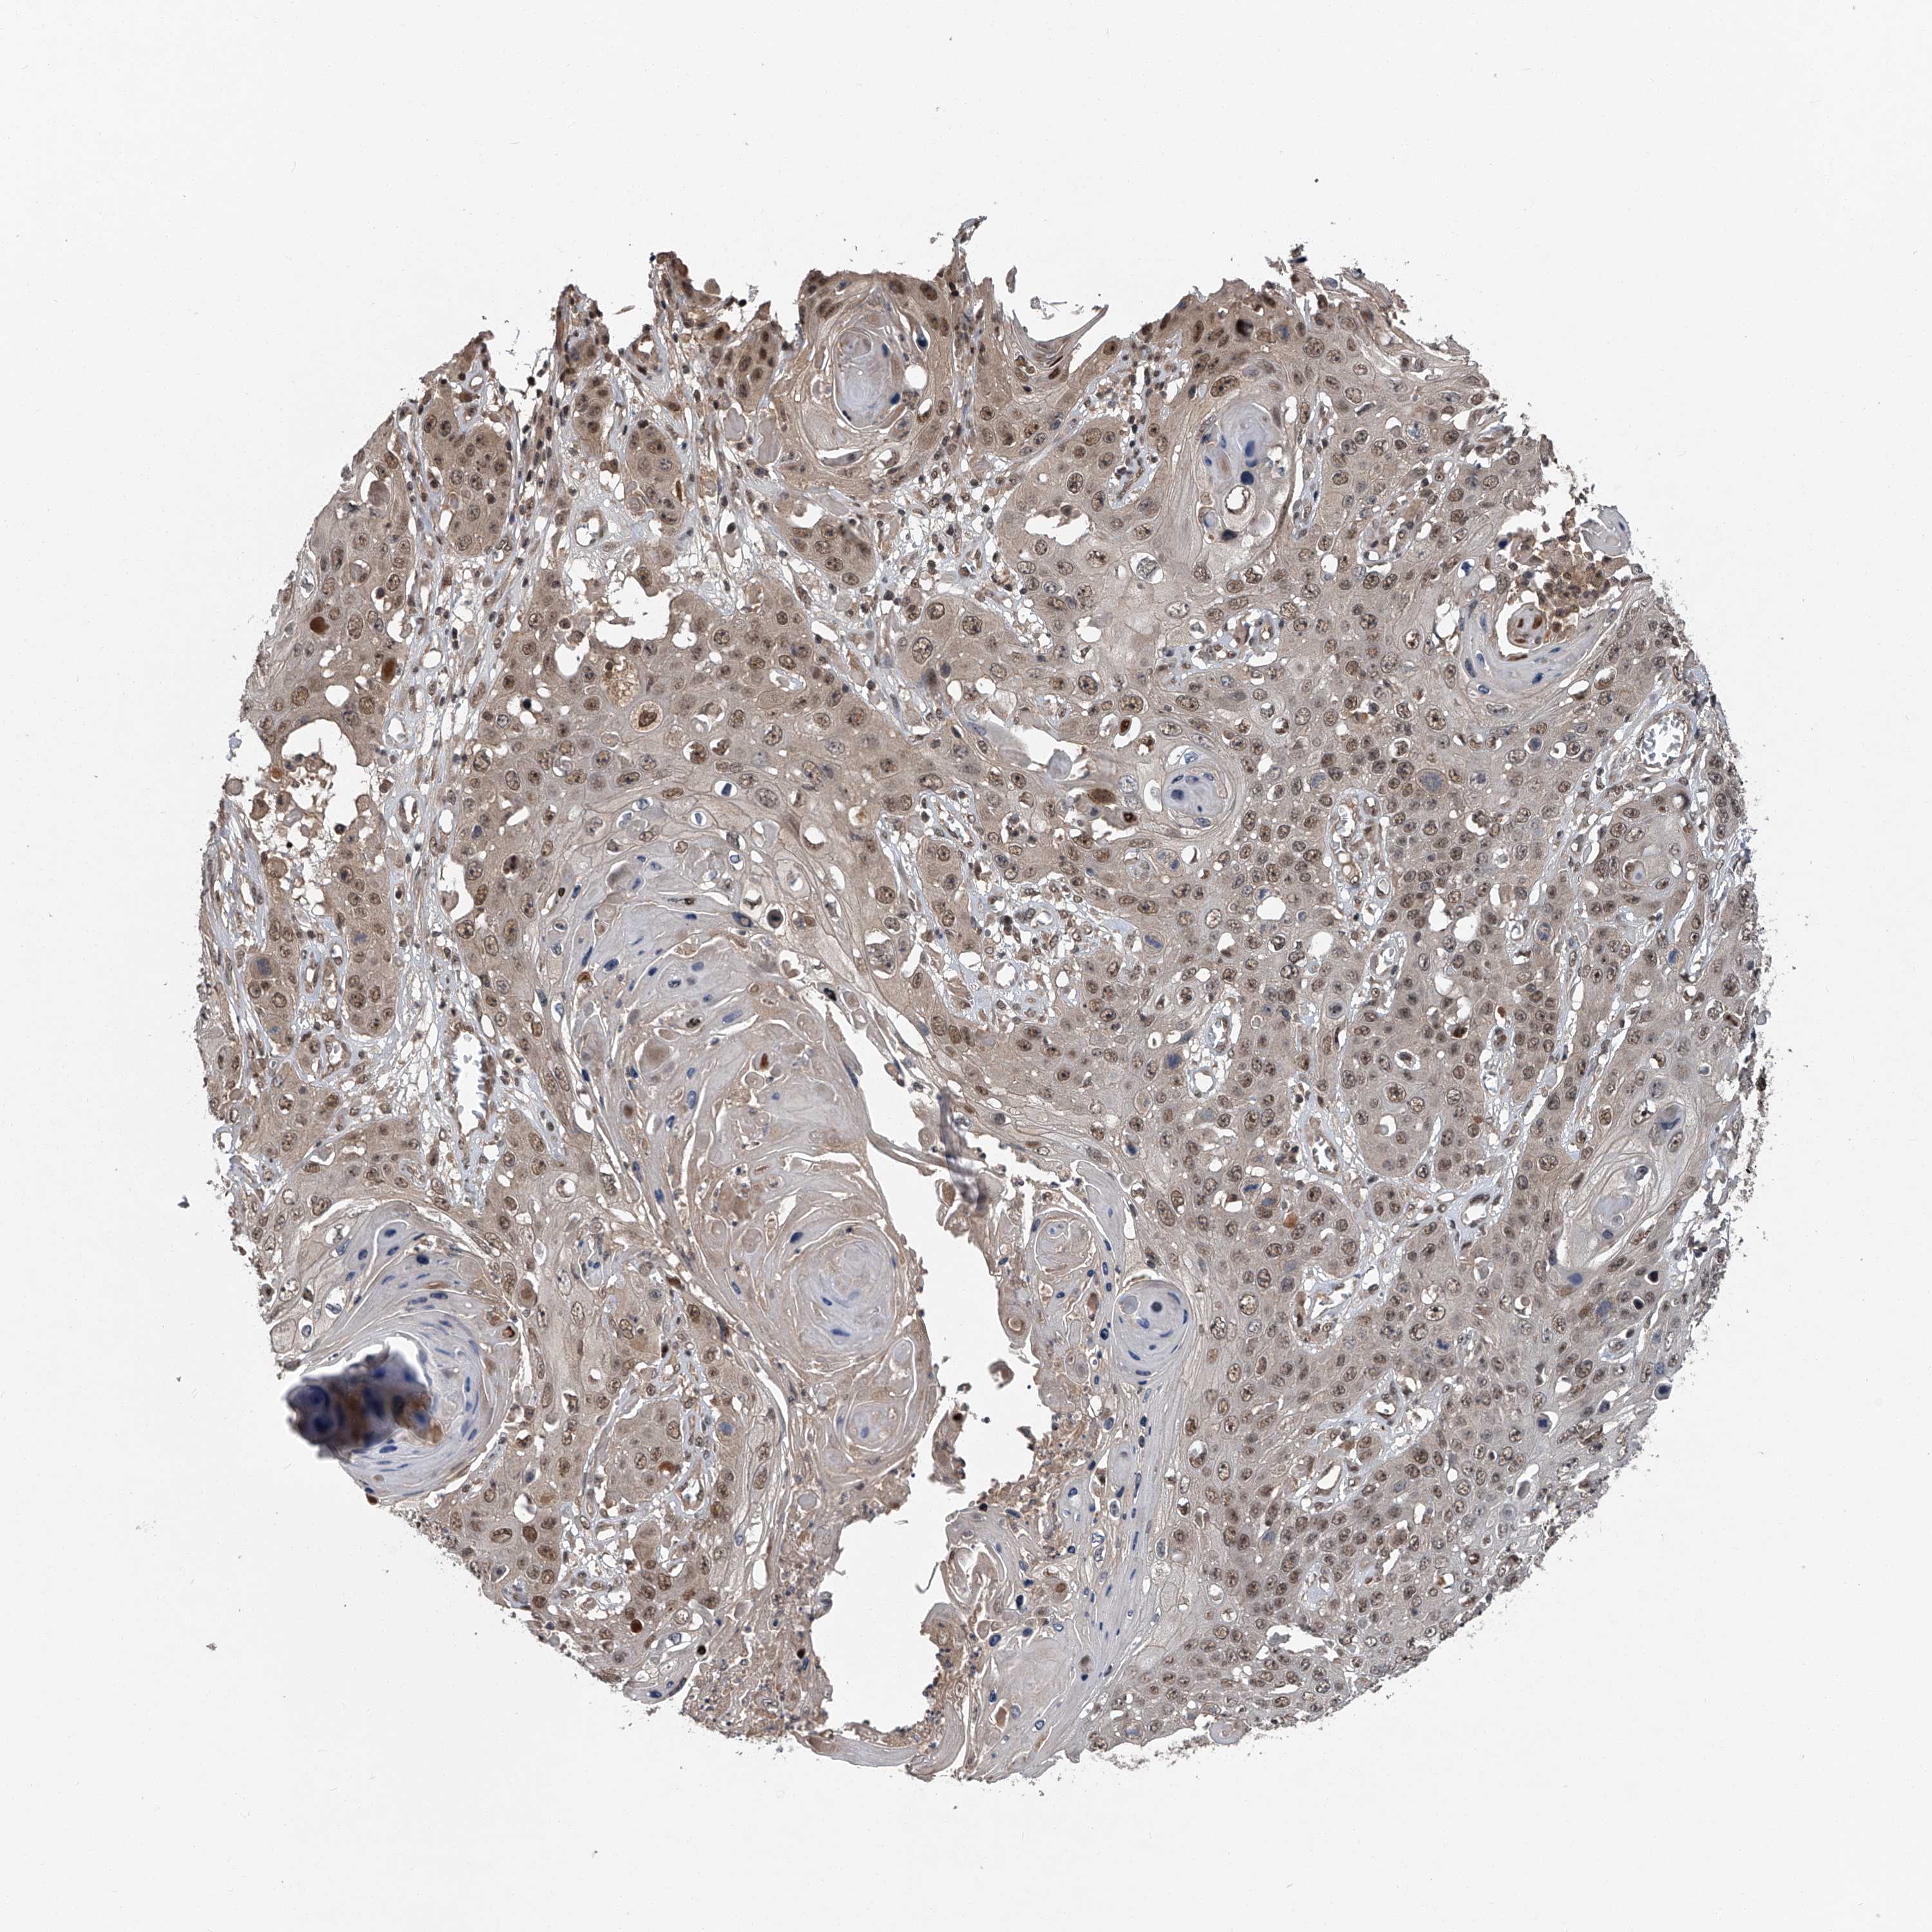

SKIN CANCER - Protein expressioni

A mouse-over function shows sample information and annotation data. Click on an image to view it in a full screen mode. Samples can be filtered based on level of antibody staining by selecting one or several of the following categories: high, medium, low and not detected. The assay and annotation is described here.

Antibody staining in the annotated cell types in the current human tissue is reported as not detected, low, medium, or high, based on conventional immunohistochemistry profiling in selected tissues. This score is based on the combination of the staining intensity and fraction of stained cells.

Each image is clickable and will lead to virtual microscopy that enables deeper exploration of all samples and also displays staining intensity scores, fraction scores and subcellular localization as well as patient and tissue information for each sample.

Antibody HPA031123

Staining

High

Medium

Low

Not detected

Intensity

Strong

Moderate

Weak

Negative

Quantity

>75%

75%-25%

<25%

None

Location

Nuclear

Cytoplasmic/membranous

Cytoplasmic/membranous,nuclear

Squamous cell carcinoma, NOS